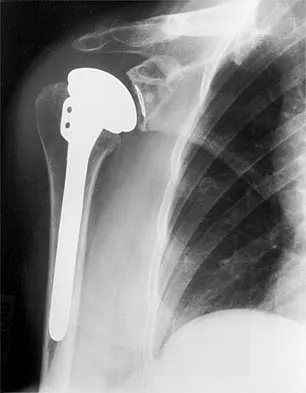

Figure 36 shows the radiograph of a patient who has hip pain and is unable to ambulate. What is the most appropriate management for this patient?

Explanation

The patient has a periprosthetic fracture of the greater trochanter - Vancouver A. The reason for the fracture of the greater trochanter is the extensive periarticular osteolysis that has occurred as a result of polyethylene wear. The latter is demonstrated by eccentric seating of the large femoral head in the acetabulum. The most appropriate management is to reverse the osteolysis process, which involves exchange of the acetabular liner with or without revision of the other components depending on their fixation and position. The greater trochanter can also be fixed during revision surgery. Duncan CP, Masri BA: Fractures of the femur after hip replacement. Instr Course Lect 1995;44:293-304.